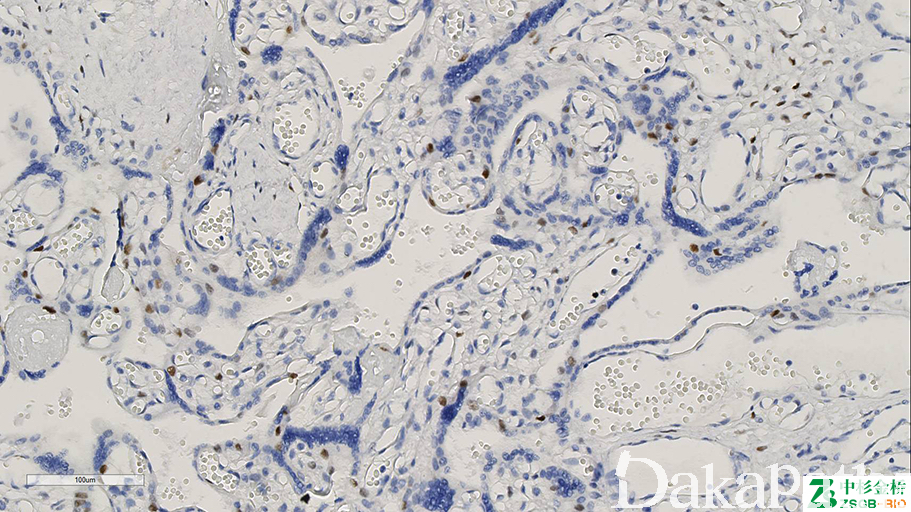

是一种细胞周期素依赖的激酶抑制剂和抑癌基因。蜕膜细胞阳性;正常胎盘细胞滋养叶细胞、中间型滋养叶细胞及绒毛间质细胞阳性;完全性葡萄胎时,细胞滋养叶细胞和绒毛间质细胞阴性。

信号定位: 胞核

完全性水泡状胎块(阴性)与部分性水泡状胎块及绒毛水肿的鉴别诊断。

几乎全部阳性(≥95%的病例阳性): 部分性水泡状胎块

几乎全部阴性(<5%的病例阳性): 完全性水泡状胎块